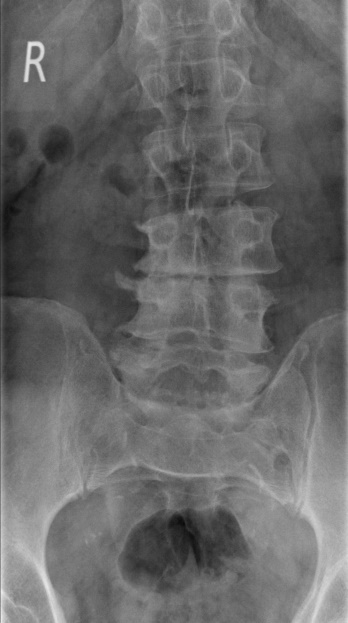

Verletzung der Wirbelsäule

Wenn es sich nicht nur um eine Zerrung oder Verstauchung handelt, sondern um einen Bruch von Wirbelkörpern, dann muss meistens schnell gehandelt werden. Neben den gängigen Standardoperationsverfahren mit Titanimplantaten zum Wirbelkörperersatz können wir in unserem Haus auch minimalinvasive Operationen anbieten.

Beispiel Verletzung der Wirbelsäule